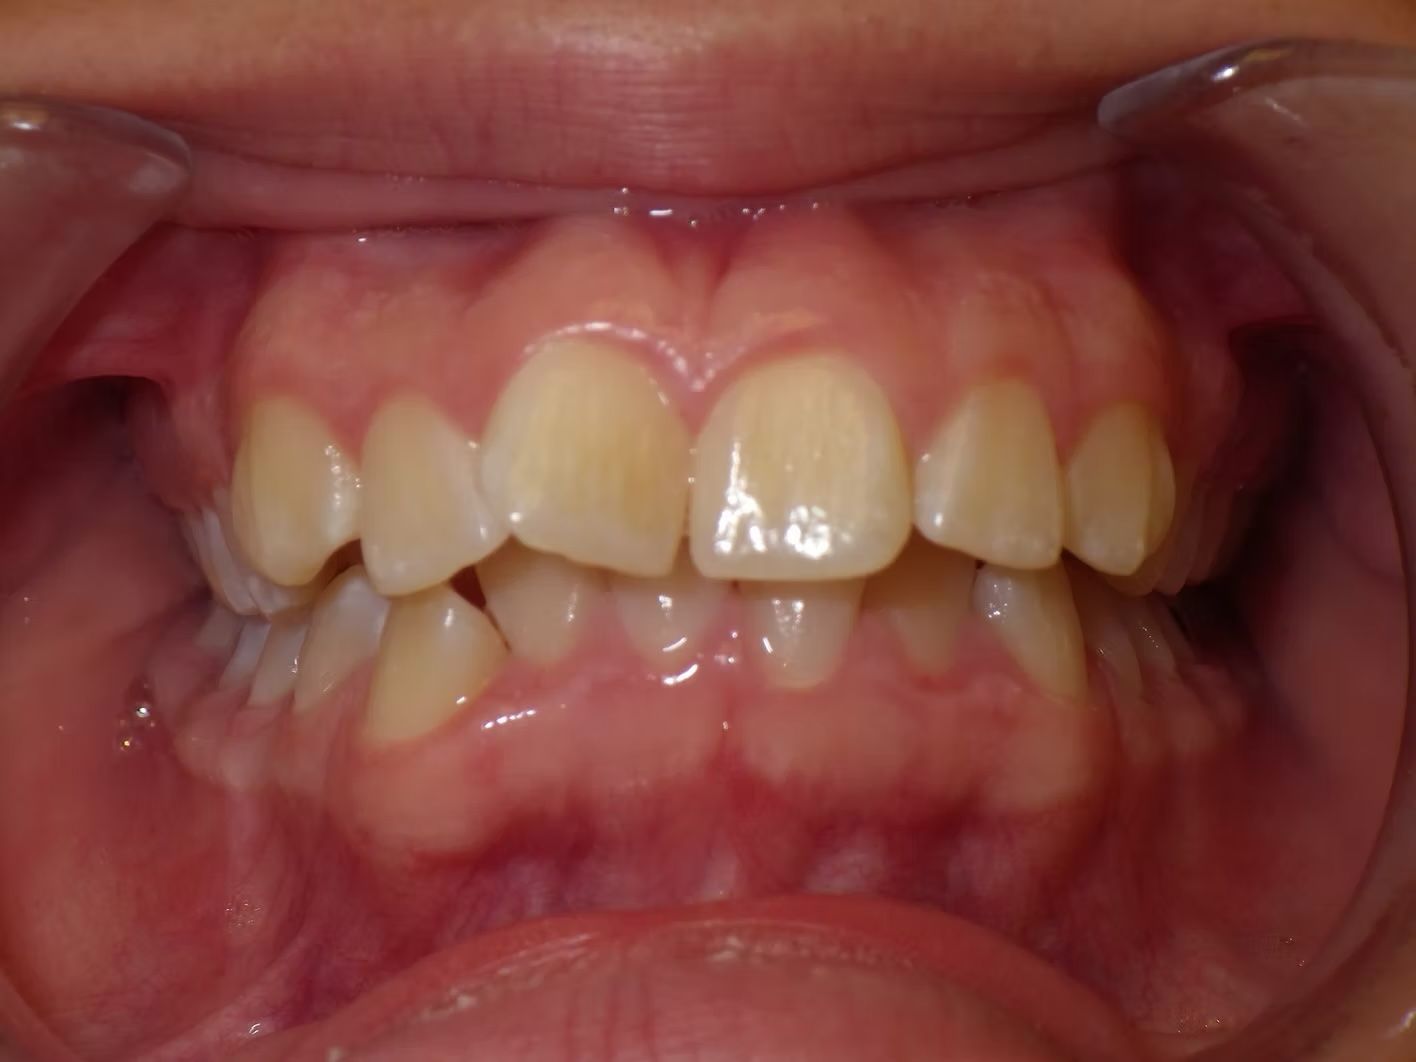

AMBER

Amber, began treatment with Dr. Bret because she didn't like that her front teeth overlapped each other. She had narrow top and bottom dental arches with severe crowding of her upper and lower teeth. She was treated with braces on the upper and lower teeth, and we used the braces to widen the smile. What a change!